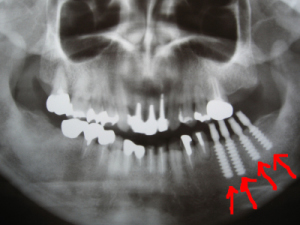

左下に歯がないためインプラントを希望 |